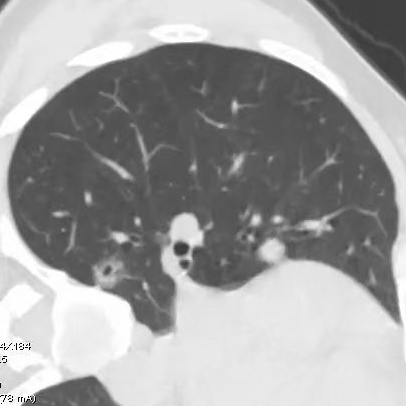

健康直通车: 健康是生命的宝贵财富,也是幸福生活的基石。为了更好地服务广大百姓,传播健康知识,葫芦岛市第二人民医院推出“健康直通车”专题栏目,将专业的医学知识以通俗易懂的方式传递给每一位市民,掌握科学的疾病预防方法,共同构筑健康中国的坚实基石。 什么是肺结节 肺结节是指肺内直径小于或等于3cm的类圆形或不规则形病灶,影像学表现为密度增高的阴影。大于3cm的称肿块。肺结节依其密度不同可分为实性结节、部分实性结节、磨玻璃结节,其中部分实性结节的恶性可能性最大,磨玻璃结节次之,实性结节尤其是小的实性结节结节最可能是良性的。 肺结节的常见病因 1、良性(约90%) 🔸 感染:结核、真菌、细菌性肺炎后遗留的瘢痕; 🔸 非感染:错构瘤(良性肿瘤)、炎性假瘤、血管瘤等。 2、恶性(约10%) 🔸原发性肺癌(如腺癌、鳞癌); 🔸转移性肿瘤(其他器官癌症转移至肺)。 如何根据影像判断肺结节性质 1、依据结节大小判断 🔸小于0.5cm的肺结节绝大多数都是良性的,属于微小结节。即使部分小于0.5cm肺结节是恶性的,但是适当的观察不影响预后。每年复查一次胸部CT就可以。 🔸大于0.5cm持续存在的纯磨玻璃结节,观察6个月,若持续存在,不管有无进展均多数是恶性的,视患者意愿,手术可以立即做也可观察至进展再做,不影响预后。 🔸大于0.8cm的部分实性结节恶性可能性非常大,应积极评估结节边缘毛刺、分叶、胸膜凹陷等征象。 🔸若实性部分大于0.5cm,恶性率显著提高。若在3~6个月随访期间实性部分增大或者总体部分增大,都可以考虑手术切除。而即使小于0.8cm的部分实性结节也需3个月就复查对比。 2、依据肺结节形态 如CT上提示病灶形态不规则、毛刺、分叶、胸膜凹陷、空泡征、血管集束征等,符合恶性肿瘤的征象。 🔸结节与正常肺组织之间界限非常清楚的恶性可能性大。 🔸结节密度不均呈混杂密度或均匀较大纯磨玻璃结节也基本是恶性的。 🔸有胸膜牵拉(不管是肺表面的脏层胸膜还是叶间裂部位的胸膜)的恶性可能性大。 🔸结节有浅分叶、细毛刺,密度较高而与周围肺组织边界不清的恶性可能性大。 🔸磨玻璃或混合磨玻璃结节存在小空洞的恶性可能性大。 🔸影像上似慢性炎表现,而没有炎症相关的其他异常,特别当所谓炎症区域内部或一侧与正常肺组织之间界限非常清楚的基本上是恶性的。 3、从结节发展情况来看 所有随访中增大进展的都需要考虑恶性可能,不进展而持续存在的纯磨玻璃结节也需考虑恶性。 葫芦岛市第二人民医院肺结节诊治中心孙振教授深耕肺结节领域四十余载,凭借对临床实践的执着钻研与深厚积淀,在肺结节精准诊断及鉴别诊断领域形成独到见解。他系统总结海量临床病例,创新性提炼出一套科学化、规范化的肺结节全周期诊疗体系,尤其在早期微小结节的影像特征识别、良恶性风险分层等方面积累了丰富经验,为众多患者提供了精准、高效的诊疗方案。 人民医院·人民名医 孙振 主任医师 三级教授 ·葫芦岛市第二人民医院胸外科主任、肺结节诊治中心主任 ·中国医科大学客座教授 ·原央企总医院著名胸外科专家 ·辽宁省医学会胸外科委员 ·辽宁省抗癌协会肺癌专业委员会委员 ·辽宁省细胞生物学学会食管癌专业委员会理事 ·主持多项科研成果获科技成果奖、科技进步奖、国家专科奖项 医学成就 从事胸外科临床工作近40年,担任胸外科首席专家及科室主任20余年,是我省胸外科领军人物,推动肺癌、食管癌等胸部肿瘤外科的规范化诊疗,在央企总医院牵头成立了肺结节诊疗中心,率先开展CT引导下肺内小结节定位切除,既确切完整切除肺内小结节,又降低肺功能损害。 专业特色 擅长肺癌、食管癌的外科手术和综合治疗,在各类高难度胸外伤手术治疗、胸腔镜微创手术、胸腺瘤手术及复杂并发症处理方面具有高深造诣,尤其擅长肺癌早期诊断,胸部小结节CT早期肺癌的鉴别等。完成各类高难度胸外科手术5000余例,其中微创手术占比达90%,治愈率达98%,多项业务填补省内空白。 开展的高难手术 胸腔镜肺部结节微创手术、肺癌根治术、食管癌根治术、各种纵隔肿瘤切除术、胸骨后甲状腺手术及胸部复合性外伤的抢救手术等。